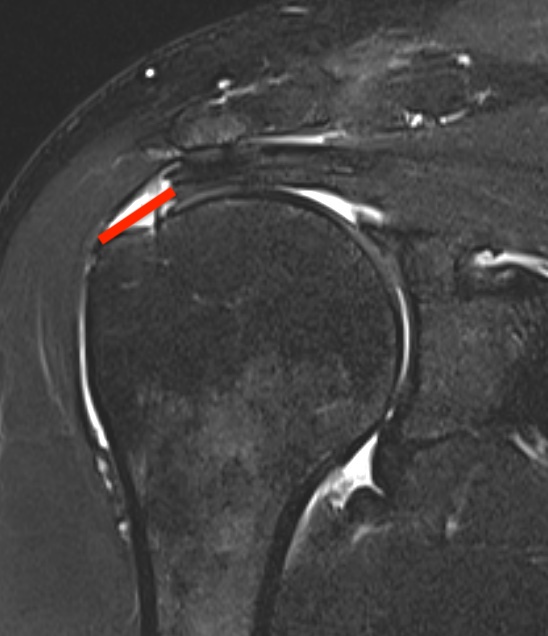

Partial bursal sided tear Partial articular sided tears

Measure tear in the coronal and sagittal plane